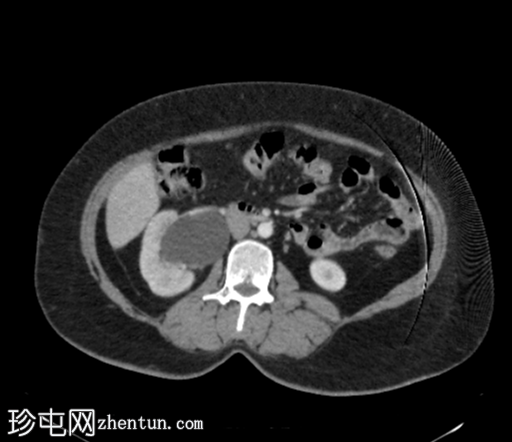

轴位肾排泄期

右肾中度肾积水,输尿管积水延伸至S4椎体水平。延迟期图像显示阴道残端扩张并充满造影剂,与右侧远端输尿管相通。

平扫图像显示左侧肾盏系统内有残留造影剂。

延迟期图像显示右侧肾盂呈斑片状强化,提示延迟性肾图,可能由远端梗阻引起。